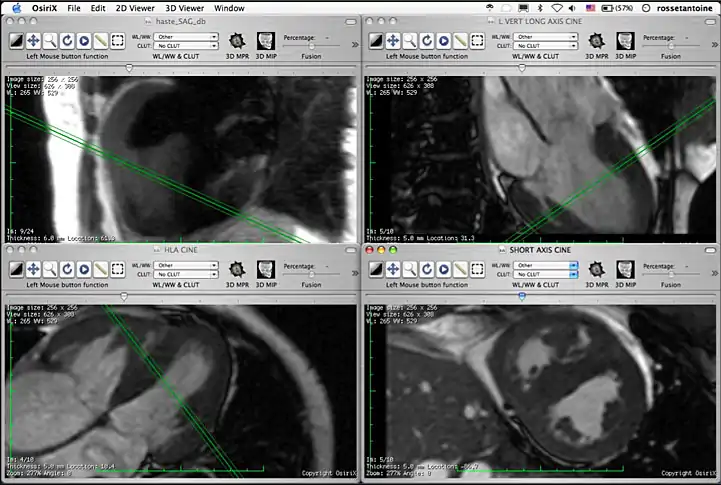

How does one simultaneously view multiple series? Select the “Tile Windows” from the “2D Viewer” menu. This function will tile all opened windows and you will be able to see all opened series at the same time.

4 series opened simultaneously. Note that if all series are from the same study, you will able to see where the slice in the series you are navigating is located on the other series.